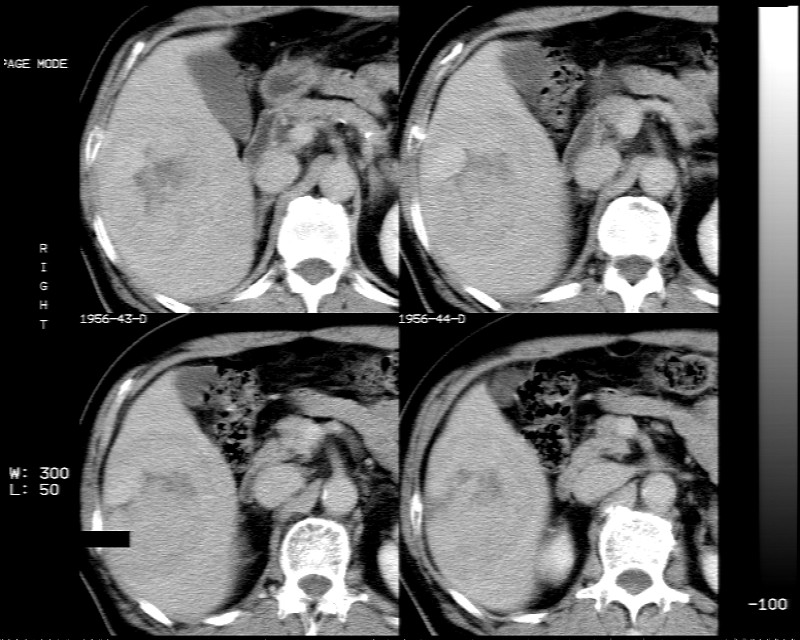

男 73岁 b超检肝右叶占位病变,afp阴性. 随访中.

肝脏右叶块状低密度影,增强后动脉期明显强化,门脉期强化减低,延迟期病灶又成低密度。考虑肝细胞癌。我认为比较典型。

低密度肿块,动脉期明显强化,可见星状低强化区,门脉期强化向中心扩展,但病灶动脉期强化最明显,门脉期及平延迟期强化减低,结合病只考虑巨大局灶性结节增生,血管瘤不除外

肝右叶块状低密度影,增强后动脉期病灶明显强化,门脉期及延迟期强化减低。

考虑血管瘤可能性大。

肝右叶巨大占位性病变,平扫呈低密度改变,增强扫描动脉期病灶周围强化,门脉期强化未退出,延时期病灶周边强化与肝实质接近,病灶中心在各期均可见星状不强化区;首先考虑局灶性结节增生可能性大,其次为血管瘤。肝癌不能完全排外(不首先考虑肝癌是因为强化不支持快进快出特点)。

平扫示:肝右后叶下段内见类圆形略低密度占位病灶,边界尚清楚,最大径约为102×71mm,ct值31~41hu。

动态增强扫描示:动脉期病灶显著不均性强化,病灶强化密度高于肝实质;平衡期病灶呈等密度;延迟扫描病灶密度略低于肝实质;三期均见占位病灶内有裂隙状无强化影。肝内胆管无扩张,腹膜后未见肿大淋巴结。

拟诊:肝右后叶下段内占位性病变,考虑为肝结节样增生。

建议进一步检查(mri/或穿刺活检),不排外肝ca。